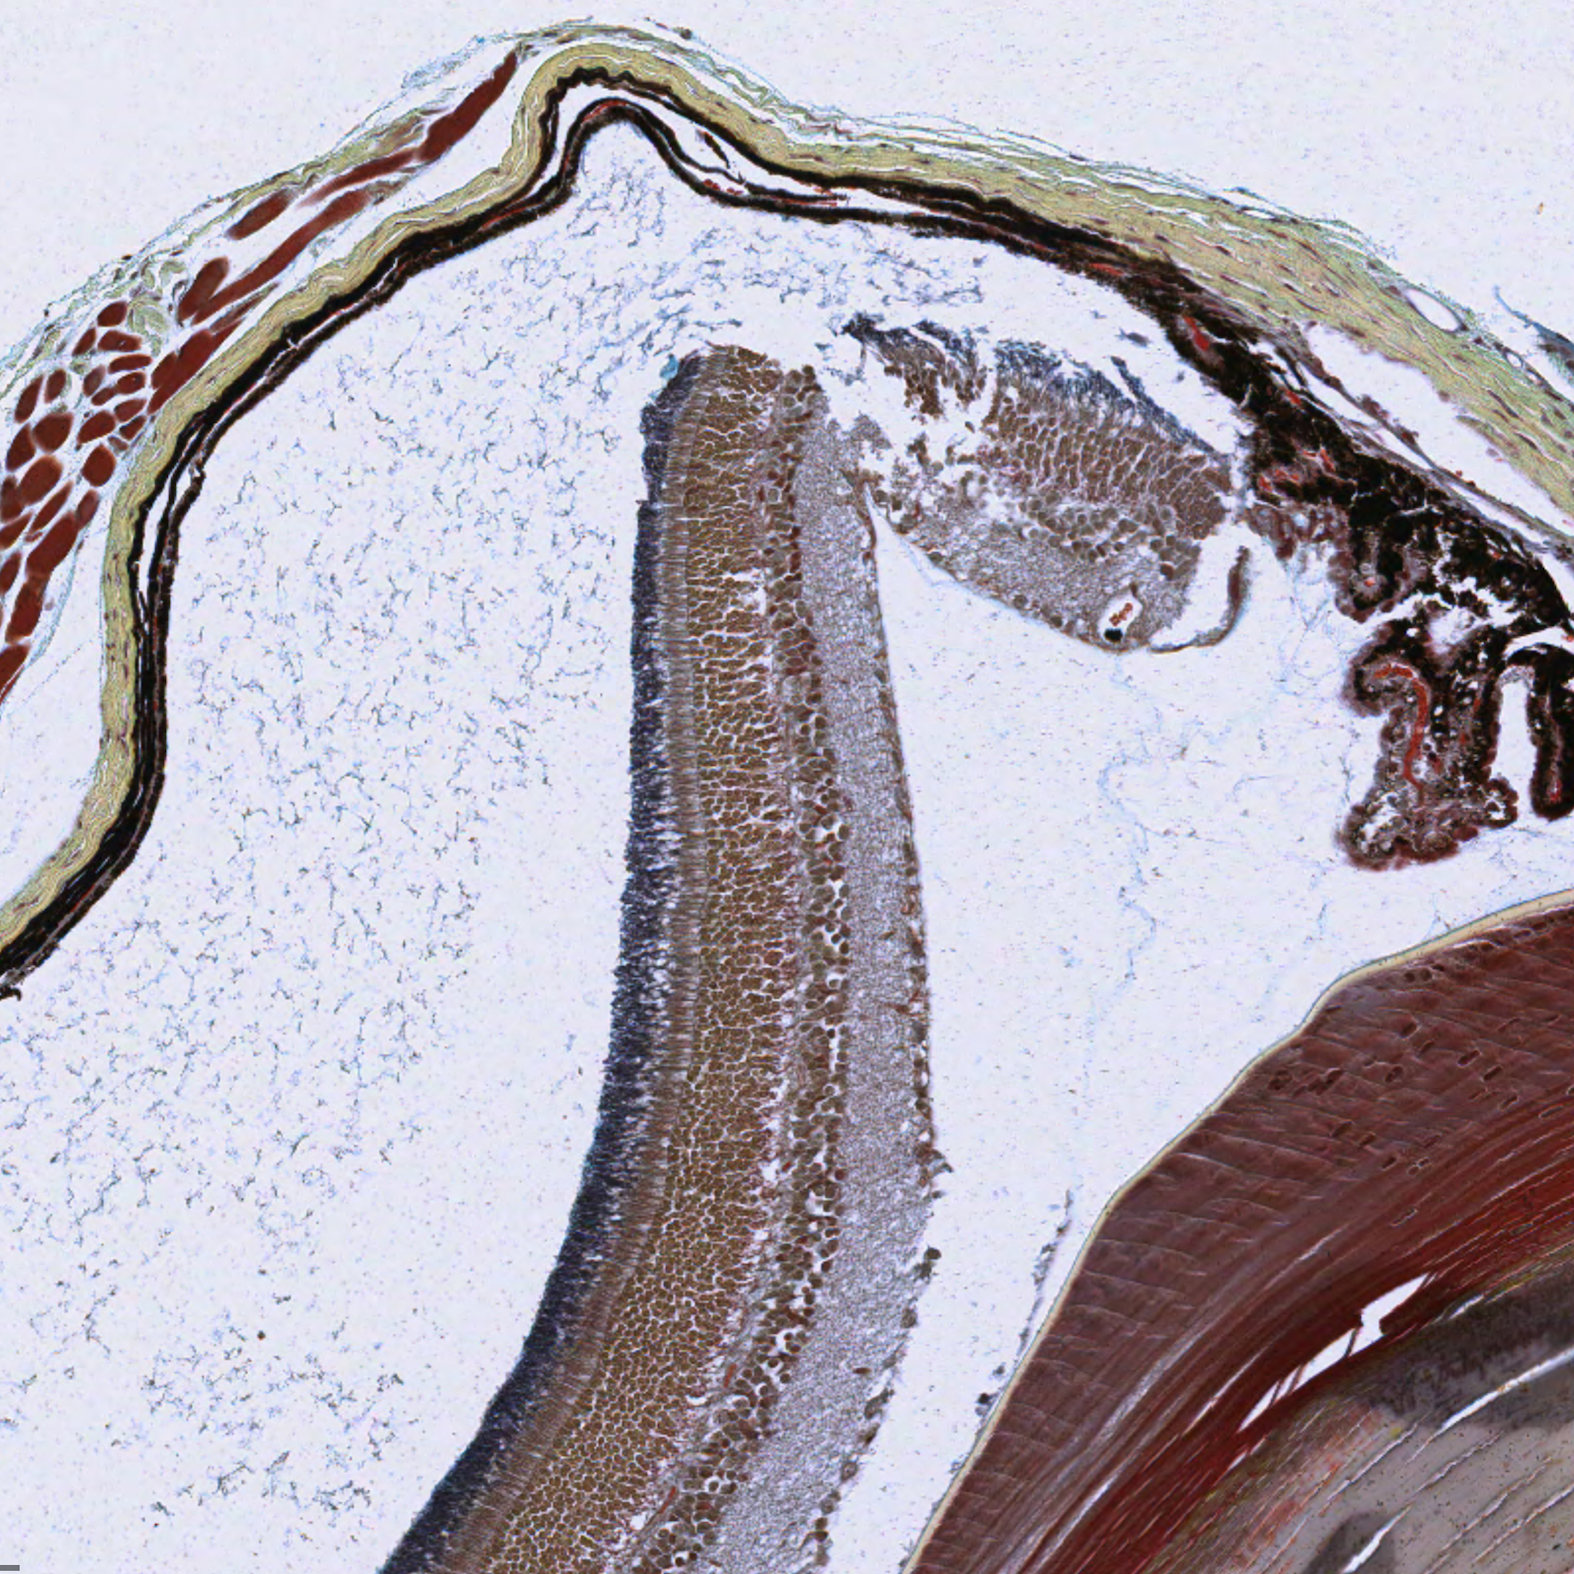

Retina

| Eye_Retina_H&E_02.svs Eye_Retina_H&E_02.png |

Eye_Retina__Pen_02.svs Eye_Retina_Pen_02.png |

The corneal layers are better visualized using the pentachrome stain kit. The pentachrome stain kit also finely stains the rod cells and allows for easy differentiation of the microstructures of the retina and cornea. The pentachrome stain kit is therefore a finer stain for the fibrillar structures. However, the nuclear staining is not as strong and the inflammatory cells might be less precisely identified.